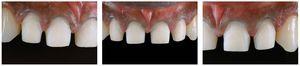

Figs. 2a a 2c. La situación antes de la operación presenta deficiencias en las proporciones de anchura y longitud de los incisivos centrales superiores, diastemas y una ligera sonrisa gingival.

Figs. 4a a 4c. Las imágenes de detalle de los dientes anteriores superiores muestran una erupción incompleta de los incisivos.